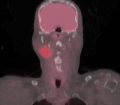

| − | + | Image:Longpetct.png|PET/CT image showing segmented hot node. | |